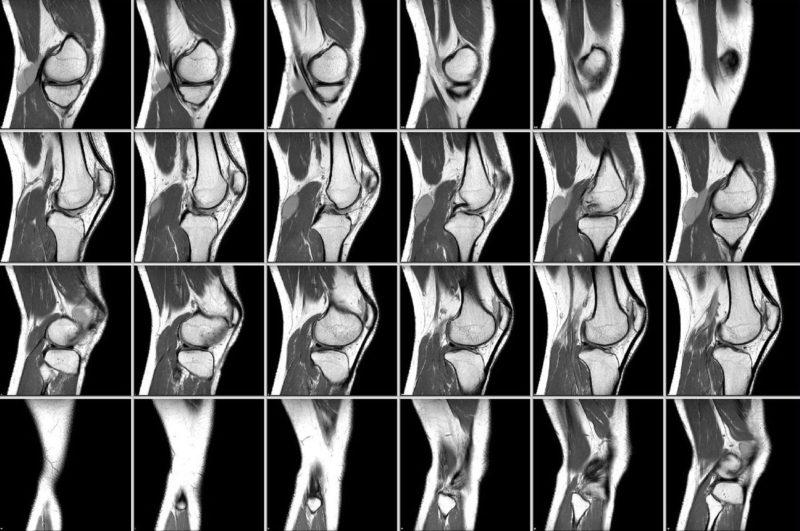

Что показывает КТ коленного сустава? В ходе исследования специалист получает черно-белые изображения исследуемой области. Также могут быть созданы трехмерные модели и срезы данного участка.

Справка. Анализ и интерпретацию полученных изображений выполняет врач, специализирующийся на лучевой диагностике.

Полученные снимки коленного сустава позволяют врачу оценить состояние костных структур и выявить следующие изменения:

- целостность костей;

- дистрофические изменения в тканях;

- инфекции, вызванные бактериями;

- наличие переломов, трещин, разрывов и надрывов связок;

- области уплотнения, разрушения и истончения костной ткани;

- опухолевые процессы в костях;

- наличие крови и жидкости в полостях;

- выявление неровностей, наростов и остеофитов;

- аномалии в развитии структур;

- наличие врожденных заболеваний.

Процесс выявления признаков патологии и составления заключения может занять от получаса до одного часа.